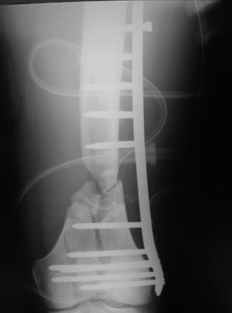

And why LISS is superior here than nail?

Look what we would have done.